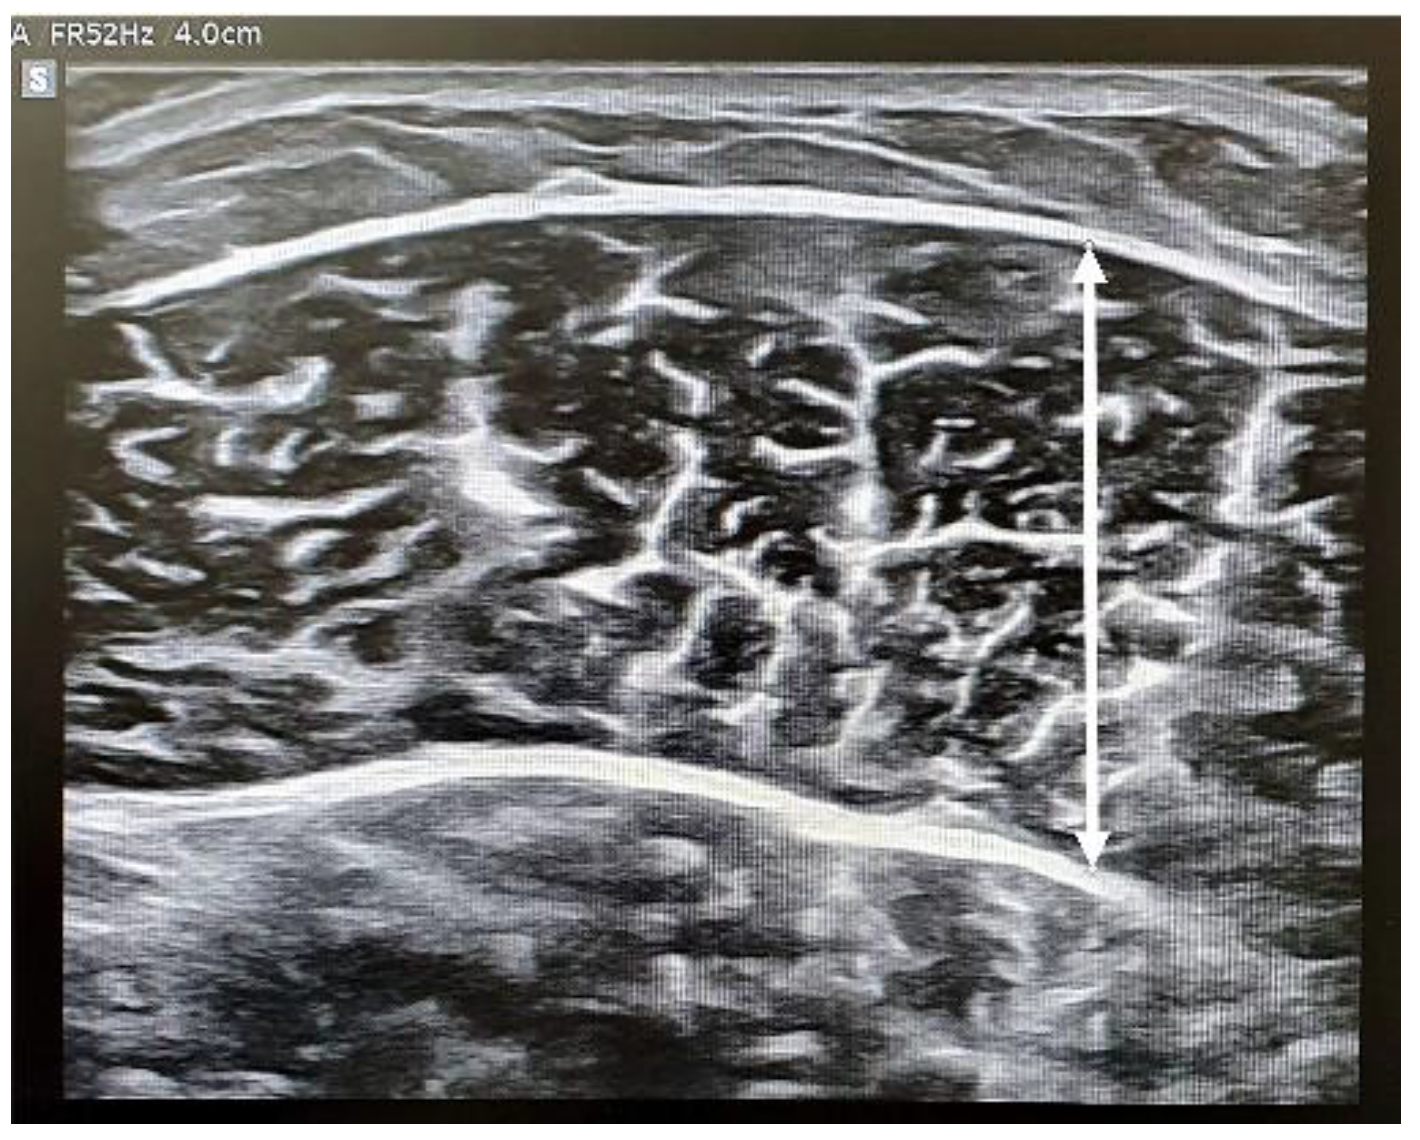

2.3.4. Stiffness and Thickness of the Muscle